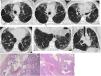

SRIF in a 66-year-old man, heavy smoker. Axial HRCT slices (images a–e) reveal mild subpleural reticulation and centrilobular nodularity, with some small peripheral cysts on the right base (image d), associated with mild ground-glass opacities (blue arrows). In addition, signs of bronchopathy secondary to smoking are observed. Histological section (image f): subpleural interstitial fibrosis (orange arrow) due to thickened, collagenised alveolar septa without inflammatory infiltrate. Alveolar spaces with discrete emphysema and intraalveolar macrophages (shorter orange arrow) (H&E 10⋅).

SRIF in a 67-year-old man, a heavy smoker, almost asymptomatic, with an obstructive spirometry pattern and a slight decrease in diffusion, which did not progress over several years. Axial HRCT slices (images a–d) showing large CLE and PSE cystic spaces with walls, some septated due to probable confluence (long blue arrow). In addition, there are numerous small peripheral cysts with thin walls (short blue arrows) that could mimic honeycombing; however, many of them are in the upper lobes, more or less separated from the pleural surface. Histological sections: image e, with subpleural emphysema (orange arrows) (H&E 5⋅) and image f, with findings of subpleural interstitial fibrosis due to thickened, collagenised alveolar septa without inflammatory infiltrate; alveolar spaces with mild emphysema (orange arrow) and intraalveolar macrophages (H&E 10⋅).

For some authors, SRIF does not have defined radiological characteristics49; for others, the pattern is similar to the RB-ILD pattern, with micronodularity and ground-glass opacities53 (Fig. 7); for others, there is mild reticulation and ground-glass opacities associated with emphysema in the upper lung fields54; “honeycombing” has even been described with the subpleural lung preserved and adjacent areas of emphysema.52 The latter coincides with the experience of Iwasawa et al.,12 who found variable patterns in HRCT in patients with a histological diagnosis of SRIF, which included thin-walled air cysts or small cysts in the areas of reticulation, in some cases very difficult to differentiate from the UIP pattern. This apparent radiological image of honeycombing can be explained by the fibrosis's location around emphysema spaces in the subpleural parenchyma.8 SRIF cysts have thin walls and a preference for the upper lobes and middle areas of the lower lobes, slightly separated from the pleural surface, unlike the honeycombing of UIP56 (Fig. 8).

CPFE in a man with accumulated tobacco consumption of 35 pack-years, with an indeterminate fibrosing histological pattern in the lung biopsy. HRCT (images a–f) reveal large emphysematous bullae (blue arrows) in the upper lobes and coarse reticular opacities with predominantly basal bronchiectasis and traction bronchiolectasis, without honeycombing (orange arrows). Histological slices (g–h) with an indeterminate fibrosing pattern. Image g: shows subpleural and bronchiolocentric fibrosis, with architectural distortion, emphysema, and bronchiolectasis (H&E 5⋅); image h: with fibrosis and emphysema with pronounced architectural distortion (H&E 5⋅).